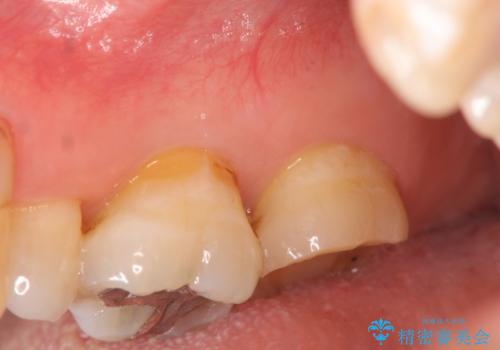

- 根管治療ののち、そのままになっていた歯のクラウン製作を希望され来院されました。

クラウンの将来的な虫歯の再発を防ぐために周囲の歯ぐきを切除することで歯の高さを出し安定した歯周環境にしたのち噛み心地の良いゴールドクラウンを製作します。

クラウンを装着した歯の虫歯の再発を防ぎ長い予後を期待するために削った箇所をしっかりとかぶせる適合の良さが必要はもちろんですが、セメントの漏洩を防ぐためにクラウンの十分な支台高径を歯周外科を行い獲得しました。